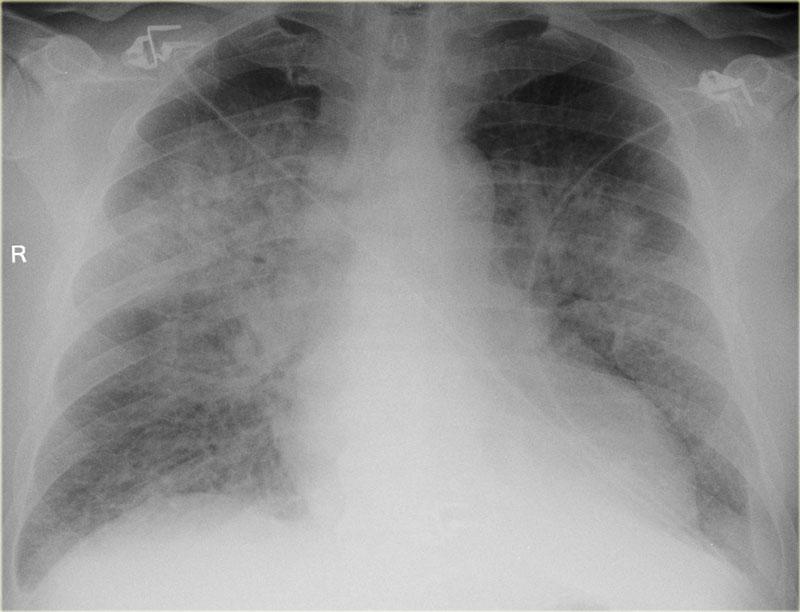

Bên trái là hình ảnh bệnh nhân nhập viện với khó thở nặng do suy tim cấp.

Các dấu hiệu sau đây gợi ý suy tim: phù phế nang với đông đặc quanh rốn phổi và dấu hiệu phế quản hơi (mũi tên vàng); tràn dịch màng phổi (mũi tên xanh lam); tĩnh mạch đơn nổi bật và độ rộng cuống mạch máu tăng (mũi tên đỏ) và bóng tim to (đầu mũi tên).

Sau điều trị, chúng ta vẫn có thể thấy bóng tim to, tràn dịch màng phổi và tái phân phối lưu lượng máu phổi, nhưng phù nề đã được giải quyết.